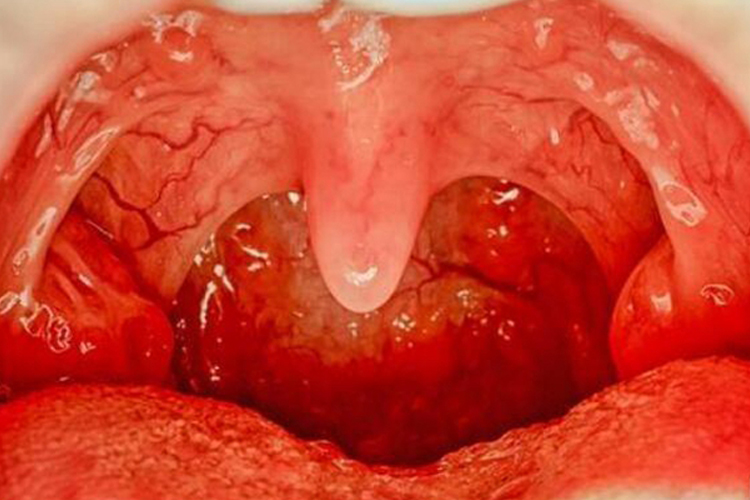

淋菌性咽炎:表现为急性咽炎或急性扁桃体炎,偶伴发热和颈淋巴结肿大,有咽干、咽痛和吞咽痛等表现。